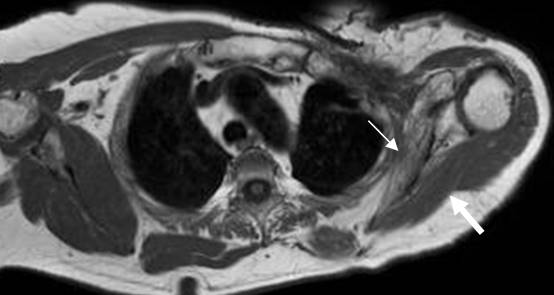

Fig 144. Ruptura de raíces.

A: RM axial y B: RM coronal en T2. Formación de seudomeningoceles en el lado derecho, por avulsión de las raíces.